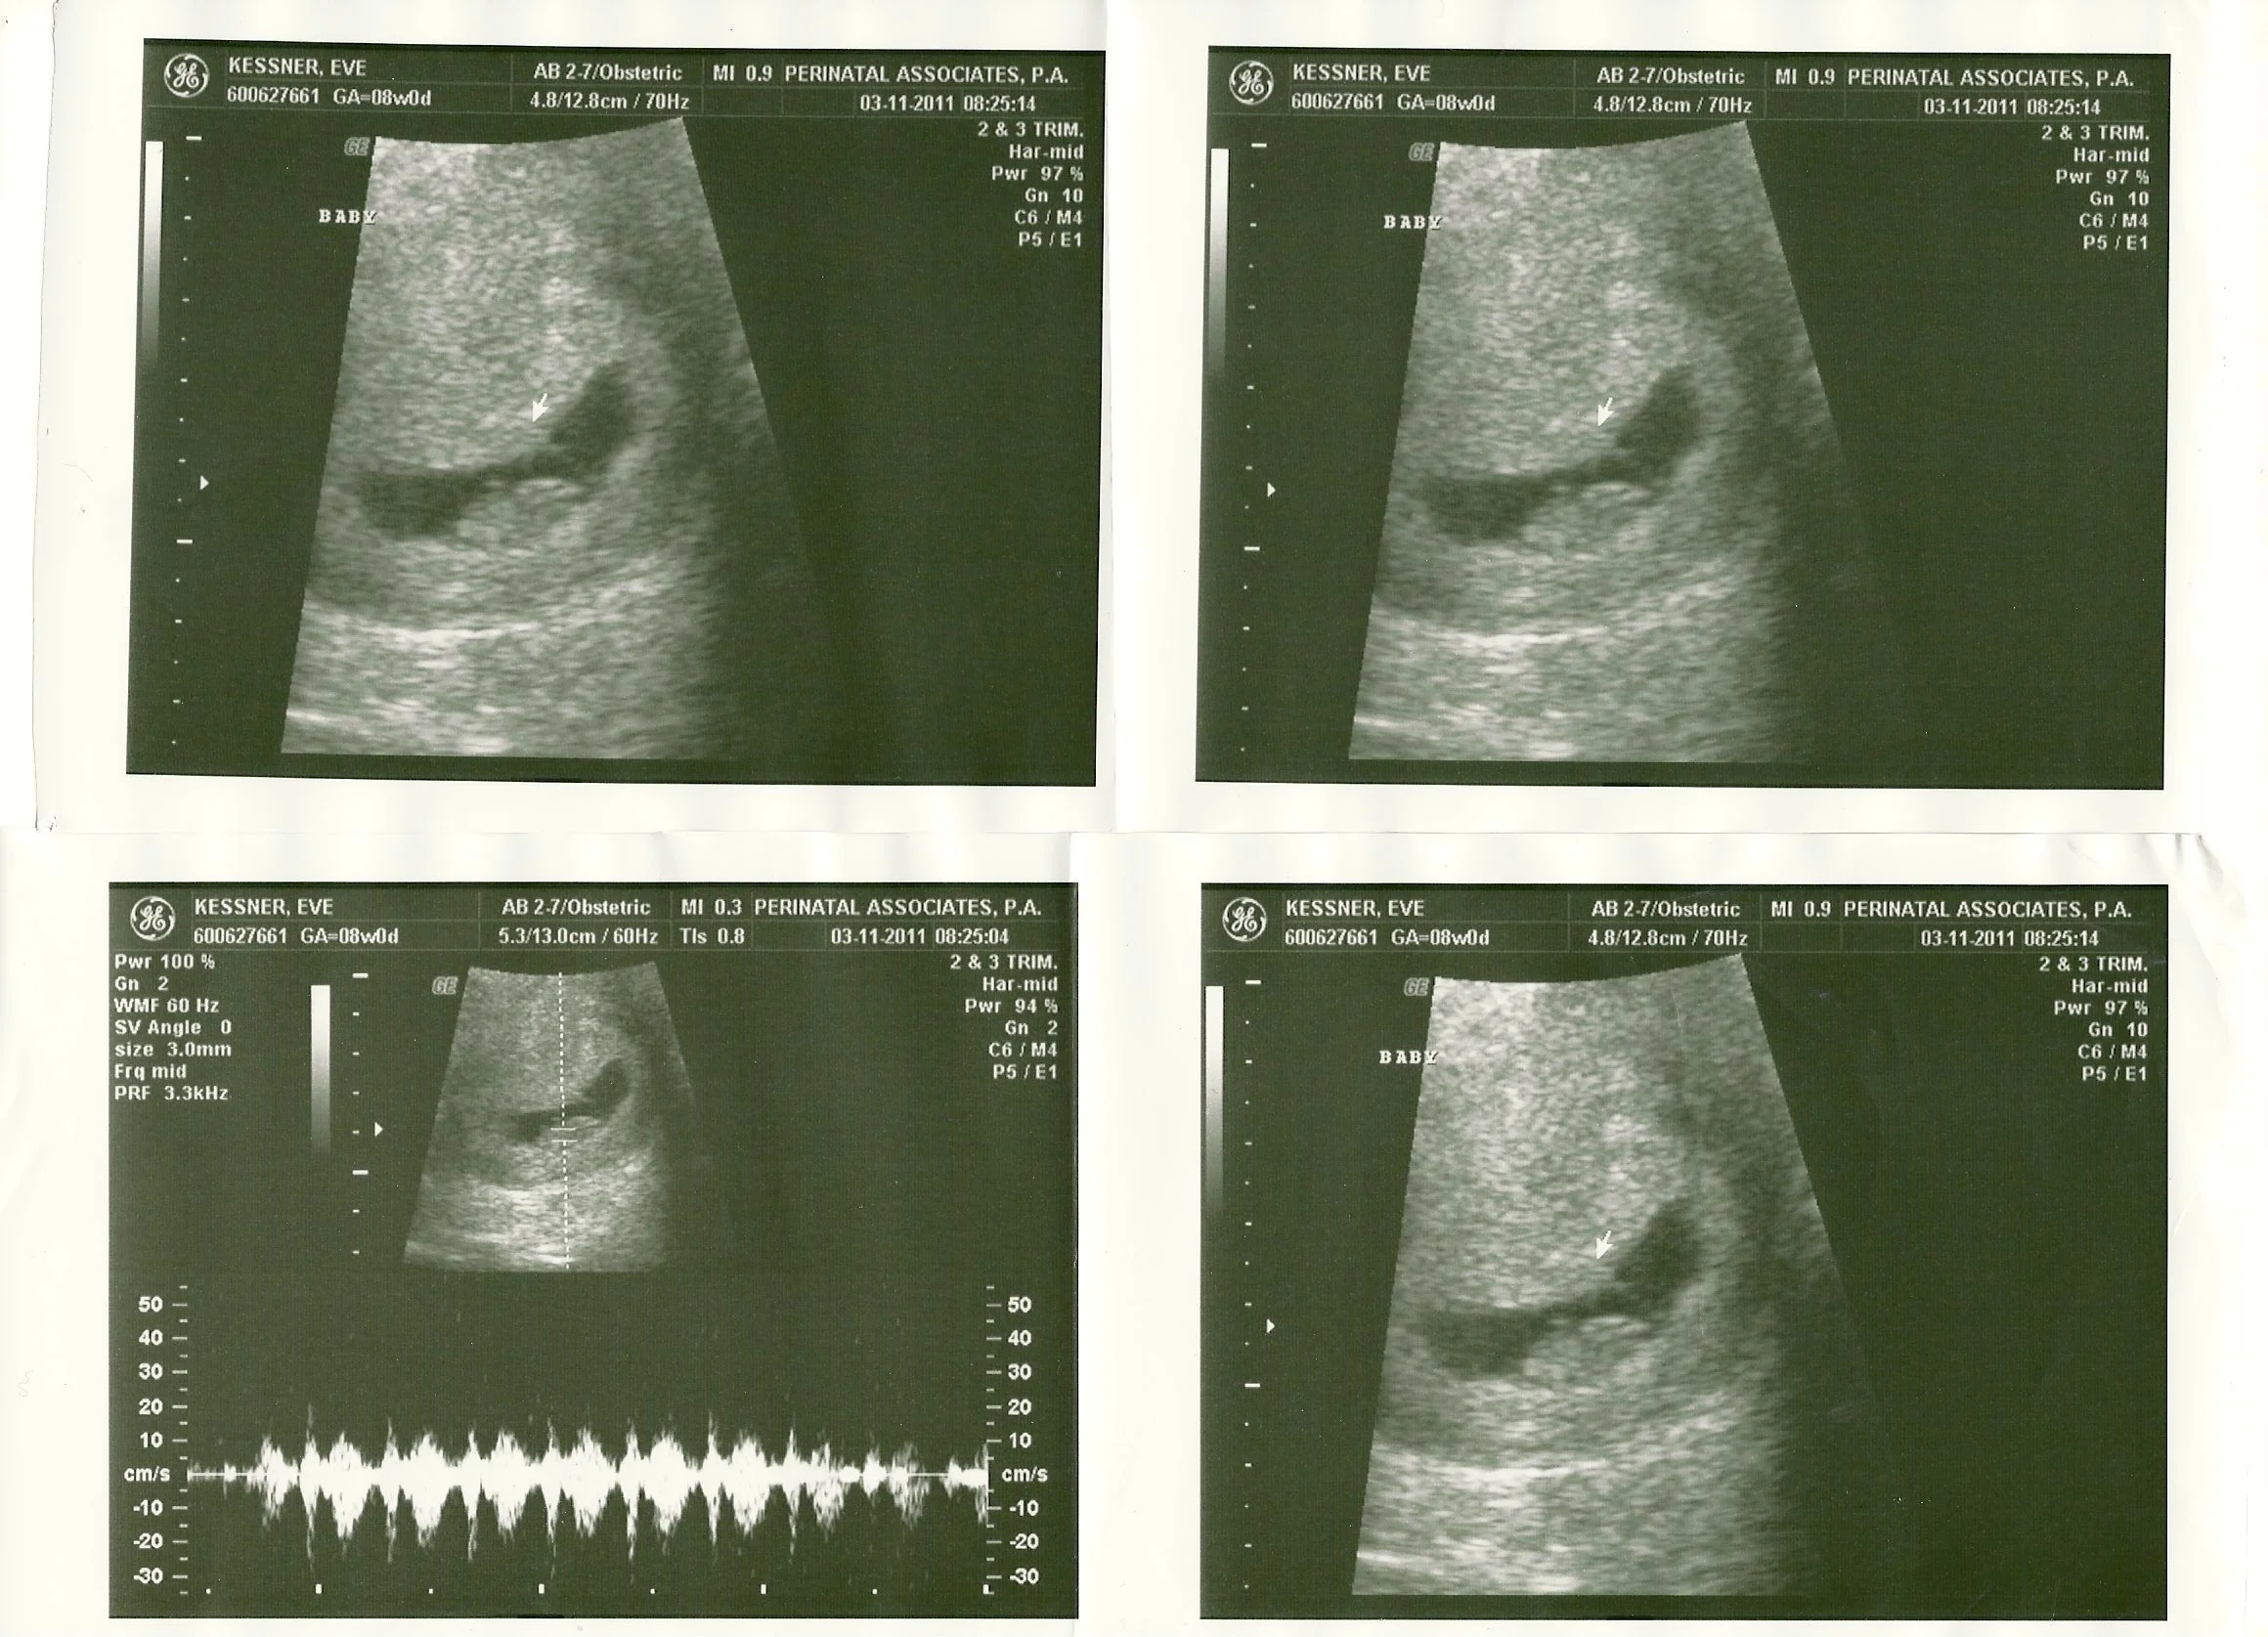

Pregnancy Week 8 PregnancyEve Lynn ChrustMarch 21, 2011Brooklyn, Brooklyn Mom, Brooklyn Vegan, Eve Lynn Kessner, Mom, Pregnancy Week 8, Sonogram, Ultrasound, vegan, Vegan MomComment